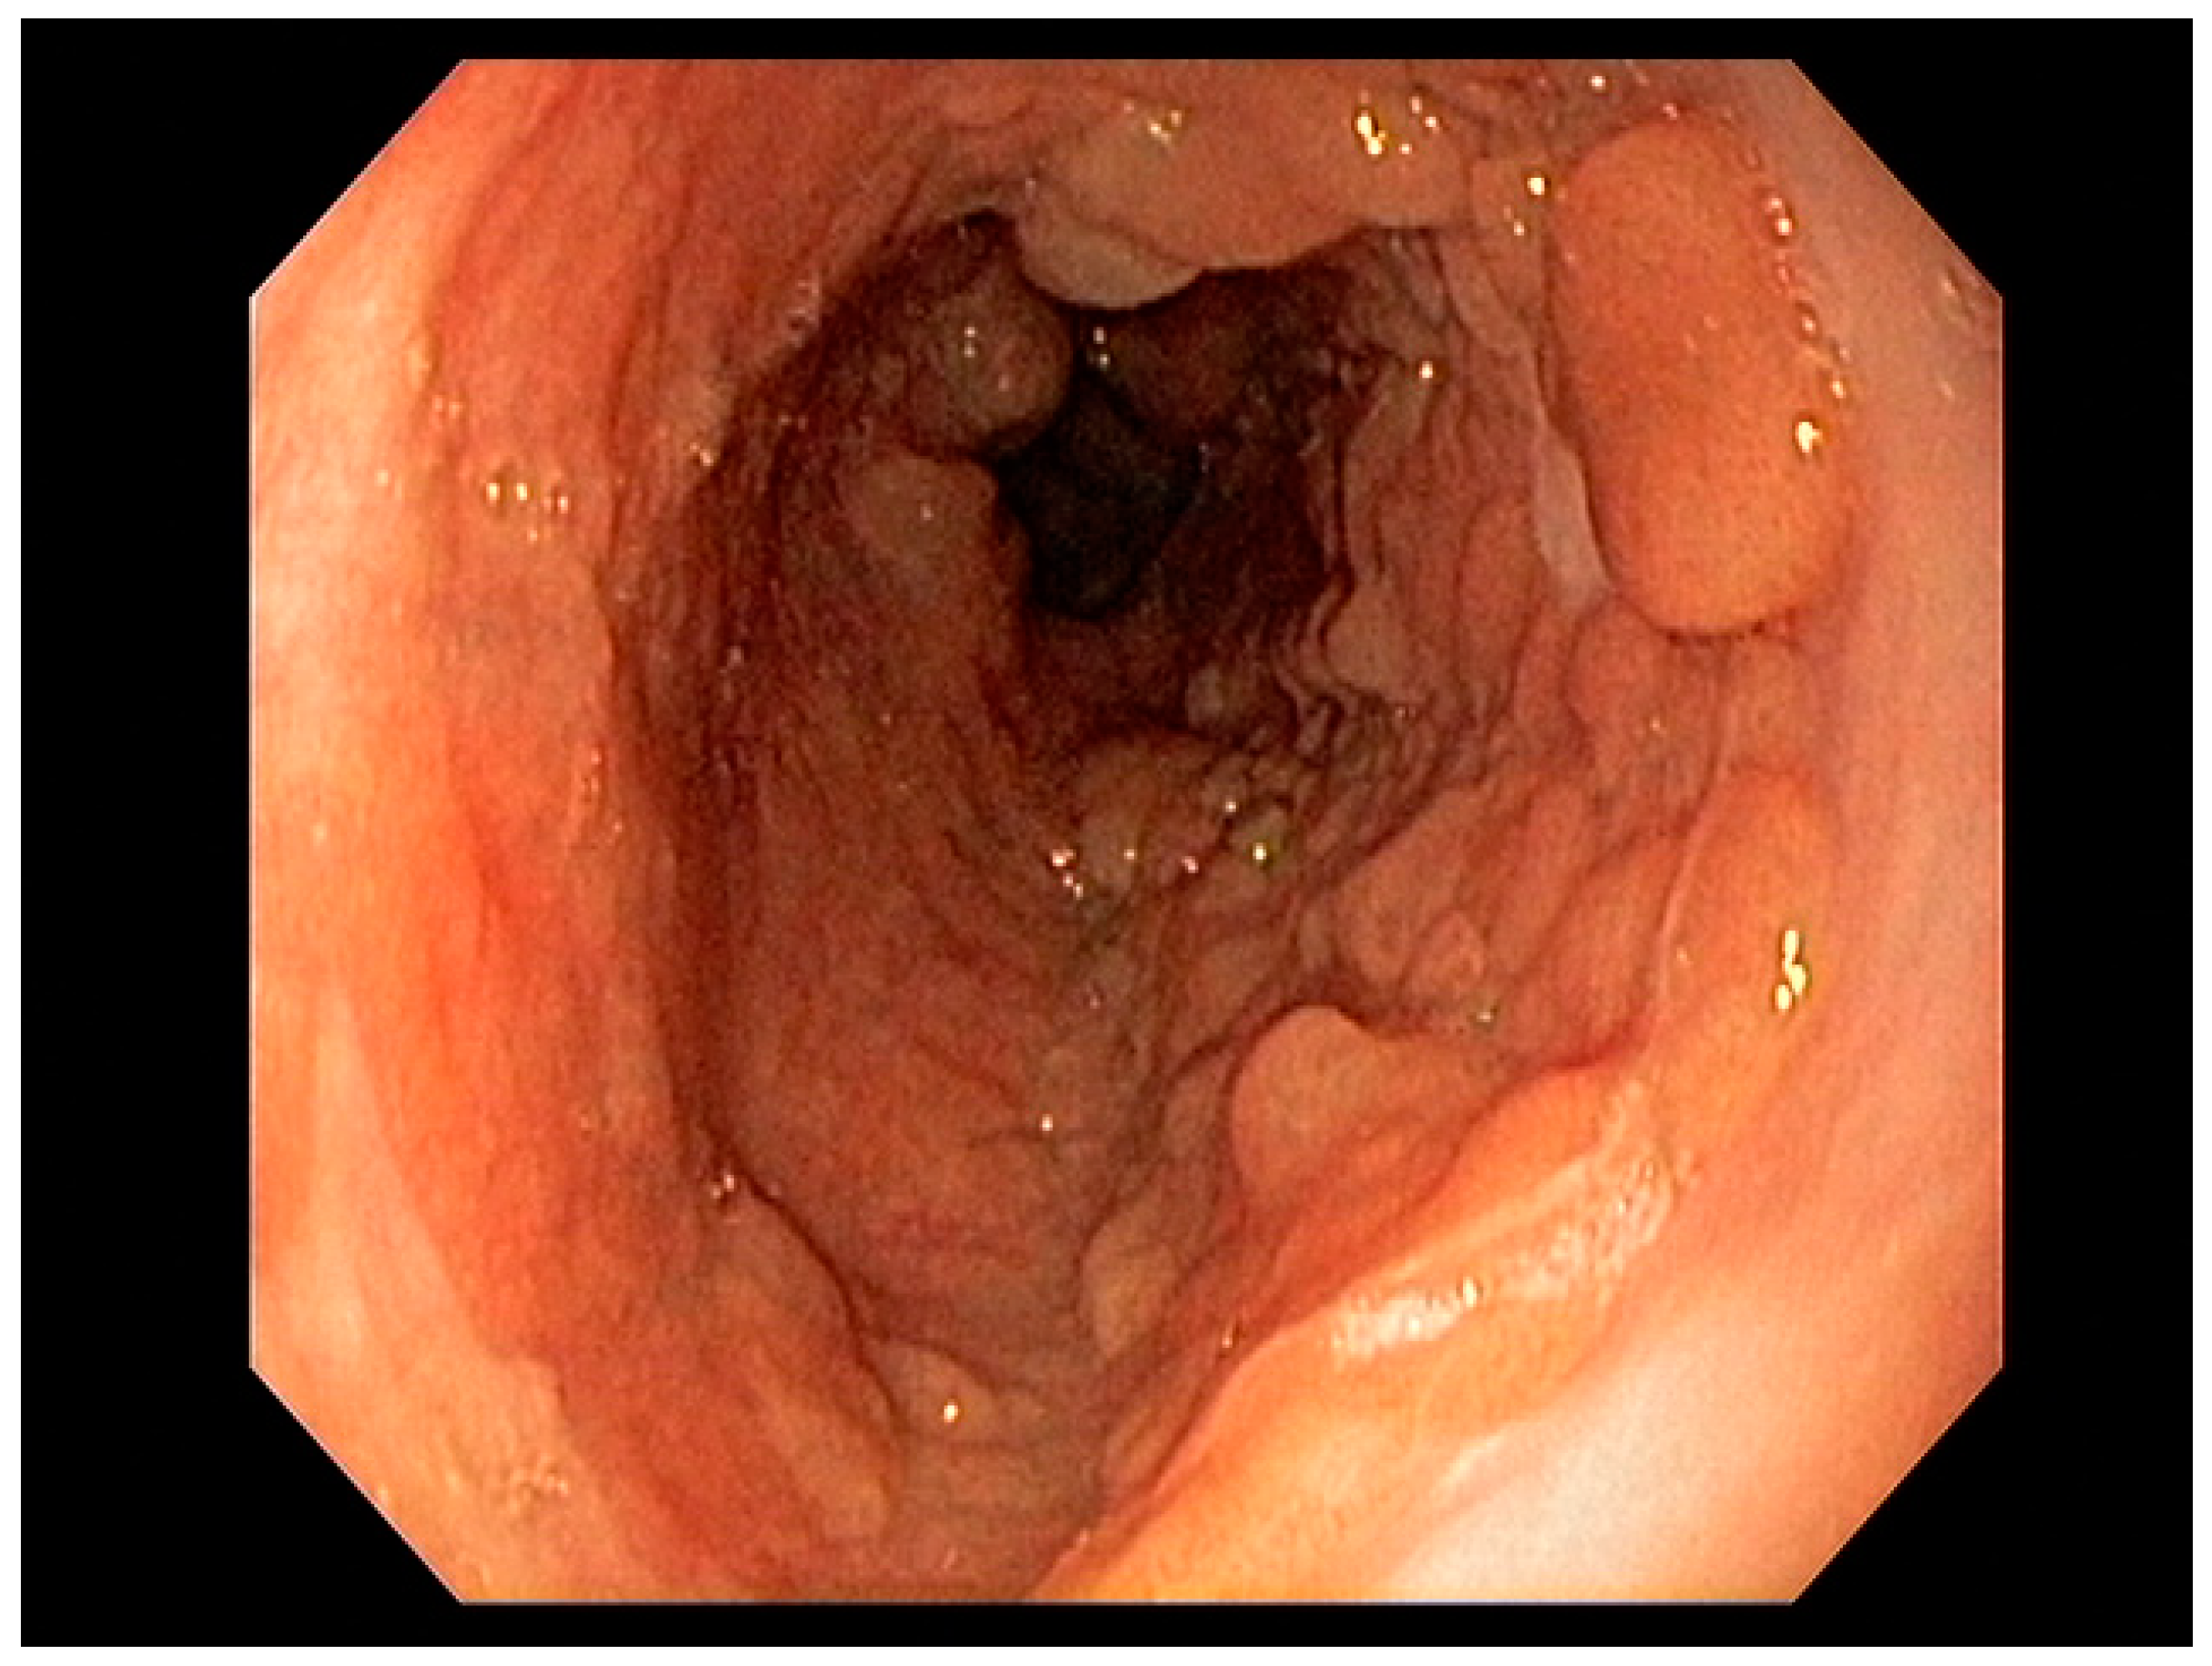

4.2. Early Gastric Cancer (EGC)

4.3. Endoscopic Ultrasound in Staging of Gastric Cancer